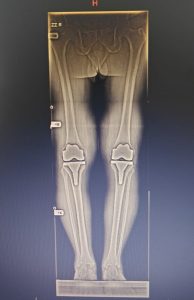

BEFORE

Robotic Knee Replacement Surgery

AFTER